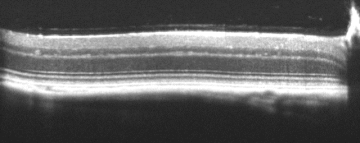

Ciliary Body

Bioptigen sdOCT Ciliary Body Image